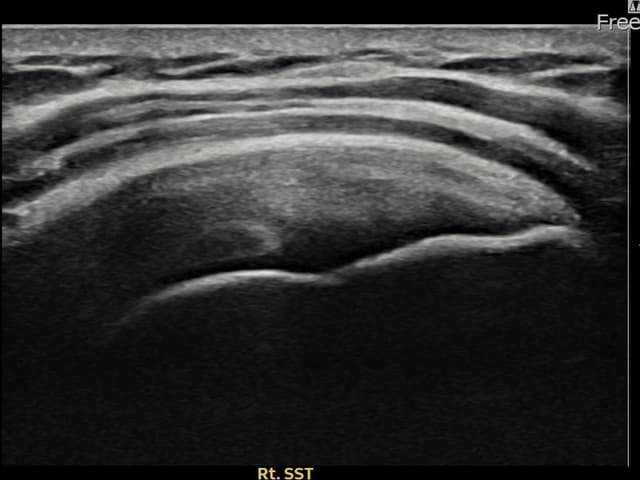

[촬영시기:22.09.19~22.12.09]

[어깨인대 축소봉합술] 우측 어깨 통증이 수개월간 지속되어 내원하셨습니다.